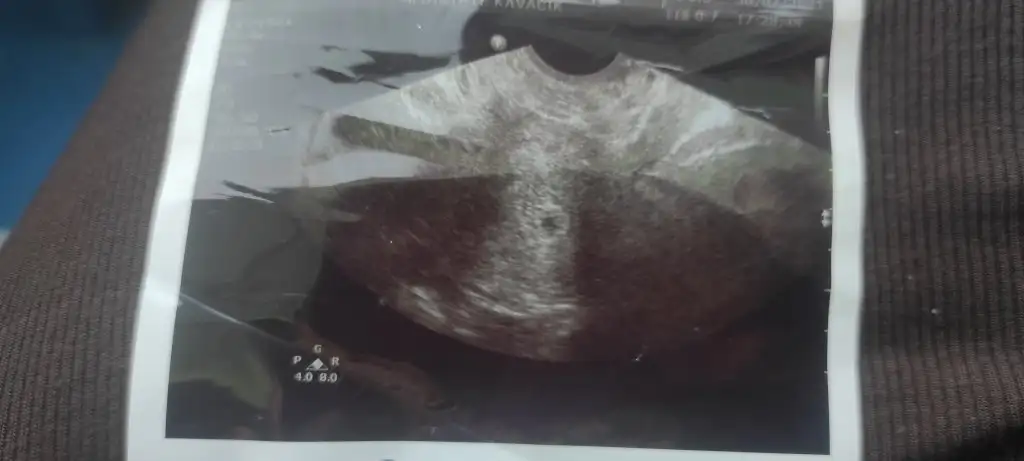

İlk kese görüntüsü de benden olsun![]()